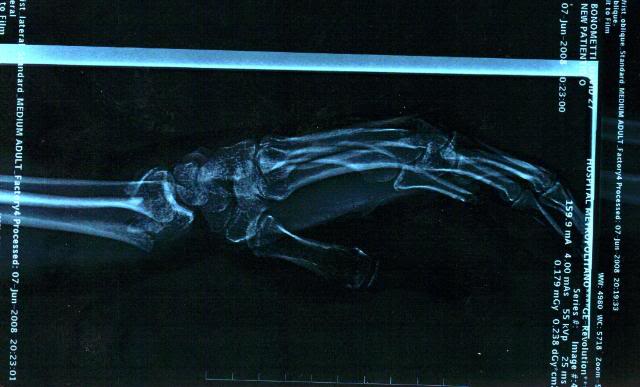

What up everyone? it's been a long time. Been very busy with the fam and getting back into everything. I just got home from a week in Wisconsin with DeCosters kids. I dislocated my good knee the first day and rode hurt the whole week. If you've picked up the last 3 issues of cycle news you've seen adds for DeCoster's kids in them. here are some pics from the show in Chile, and the x rays of my wrists when I broke them in Equador. I'm semi retireing from the pro scene, I'm tired of being gone all the time. I'm getting my personal trainers licence and going that route. I'll still do Decosters shows & local fmx demo's when I feel like it. Hope you all like the pics.

and the broken wrists